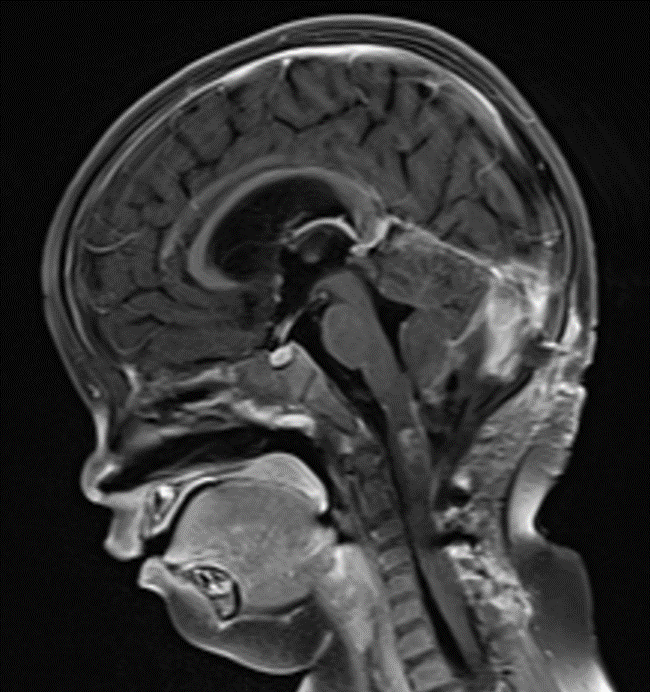

术后影像

术后MRI

然而术后恢复之路仍充满波折。因并发脑积水,患儿出现呕吐等症状,经脱水治疗效果不佳。医疗团队与家属充分沟通后,再次为阿什利施行脑室-腹腔分流术,术后脑积水显著改善。与此同时,医院为她制定并实施了系统化疗方案,历经5个周期的药物调整与精心治疗,至今年7月MRI复查显示术区强化灶已完全消失。